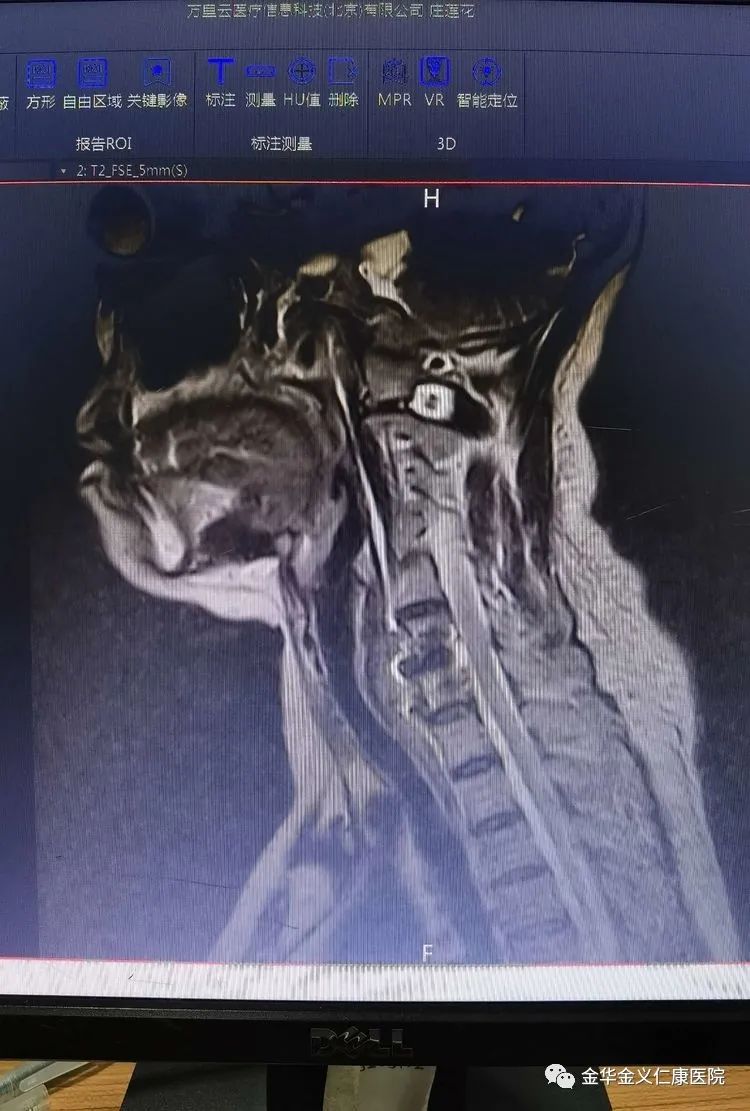

11月2号,仁康医院骨科专家门诊来了一位60多岁的大妈,举着右臂,眉头紧锁,在焦急的等待就诊。接诊的徐煜院长询问病史,了解到大妈来自塘雅镇某村,姓庄,感觉右肩部疼痛已经半年。开始疼痛不严重,就在附近卫生院配了一些药口服治疗,但是效果不明显。因为日常生活影响不大,能将就着过日子,也就没有做进一步的检查和治疗。一周前,庄大妈感觉右肩部疼痛逐渐加重,并且向上臂放射,同时感觉手指麻木。她到金华市区某医院就诊,医院诊断为颈椎病,给予吃药、针灸、理疗等治疗,但是疼痛不但没有减轻,反而越来越重。近3天来,晚上因为疼痛而辗转反侧,每晚只能睡上2、3个小时。白天只能举起手臂才能使疼痛有所减轻,放下手臂就疼痛难忍。在别人的推荐下,她来到了金义仁康医院就诊。经磁共振检查,显示庄大妈的第6、7节之间的椎间盘有严重突出并向上方脱位,右侧的神经根受压明显。

术前的颈椎磁共振